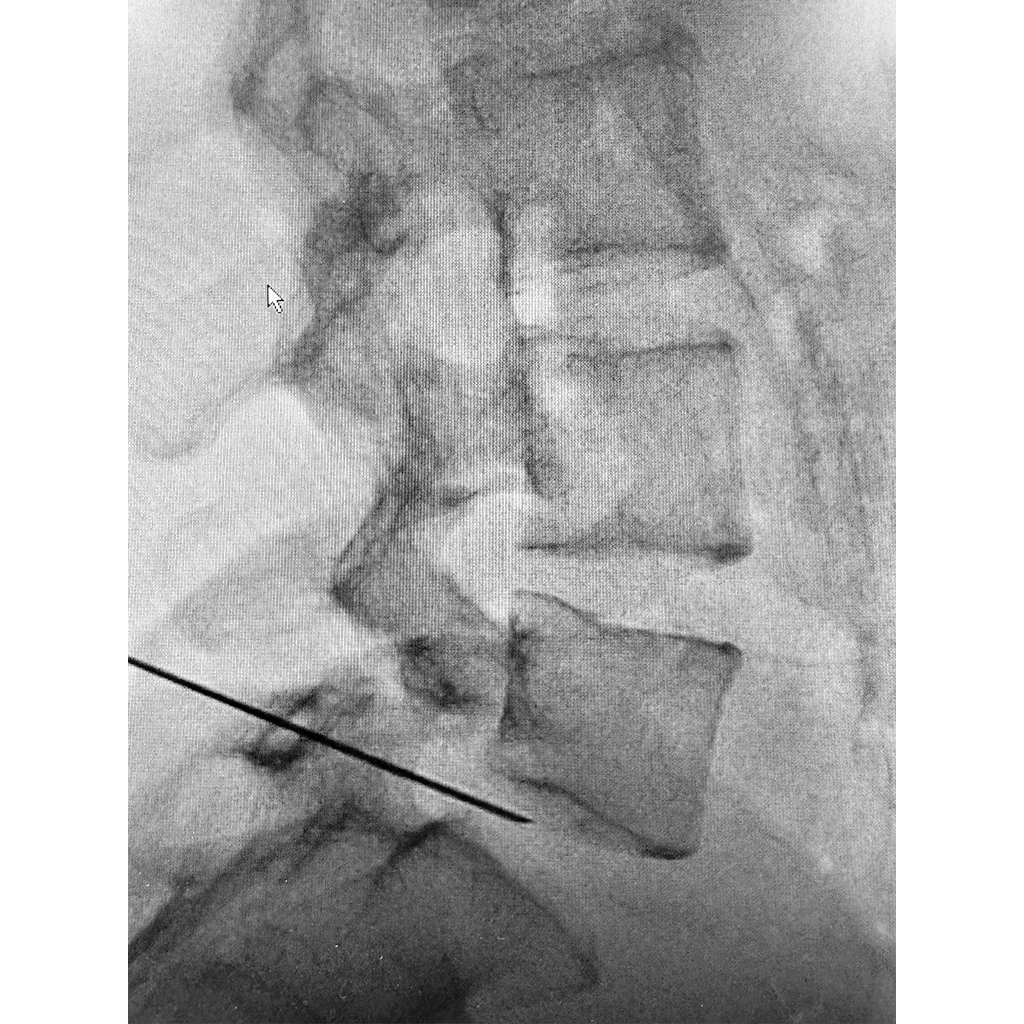

椎間板に穿刺針を挿入し、空気圧検査を行っているところです。圧は正常よりも高く、椎間板内圧の上昇が確認されてました。もちろんAnnulogram検査は陰性となります。